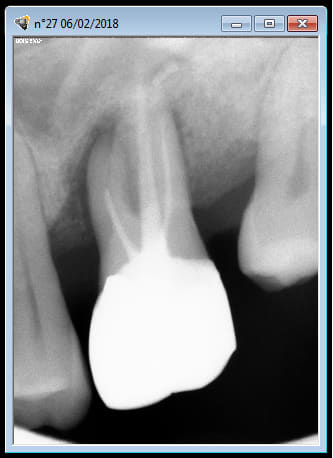

37

apres une endo de sauvage ,bien bourrée au compactor , 1 petit aller retour pour cette 37 .

pratique pour detartrer la face distale :-))

je vous tiens au courant .